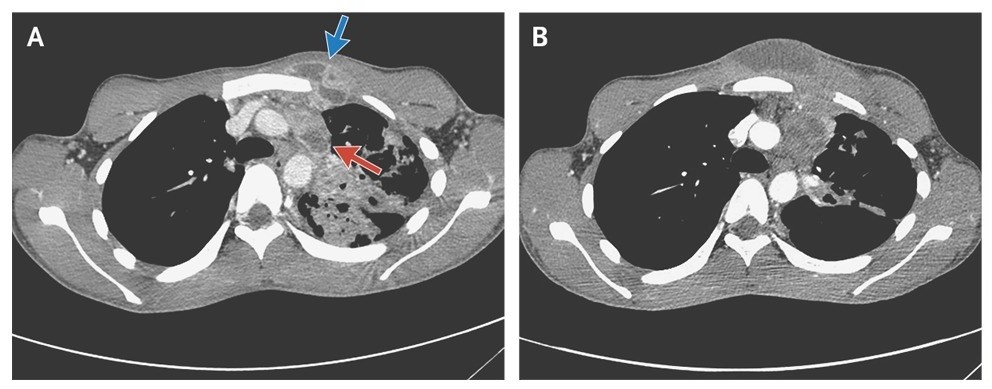

A computed tomographic (CT) scan of the chest obtained on admission showed a collar-button abscess (a subcutaneous abscess connected to a deeper abscess by a passage), consisting of an abscess in a lymph node in the left mediastinum (Panel A, red arrow) connected to a subcutaneous abscess in the anterior chest wall (Panel A, blue arrow). CT also revealed an extensive parenchymal abnormality in the left upper lobe.

The patient received 8 weeks of standard antituberculous treatment, but the infection progressed, with increased swelling, erythema, and fluctuation of the subcutaneous abscess (Panels B). The abscess was subsequently treated with open drainage.